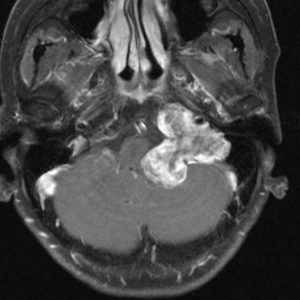

症例:小脳延髄角部のもの,聴神経腫瘍と紛らわしいもの

水頭症による頭痛,嘔吐と右聴力低下で発症しました。体側の左側の感覚低下としびれがありましたが,それはbrainstem distortionによるものでした。一見,聴神経腫瘍にみえるのですが,内耳道内に腫瘍がありません。

手術では,脳槽内迷走神経根の一部が腫瘍化したものでした。顔面神経と聴神経との剥離は容易でした。

機能的にも聴神経,舌咽神経,迷走神経は温存できました。

術後しばらくの嚥下障害は改善,迷走神経症状としての咳嗽発作が6年ほどありましたが治りました。